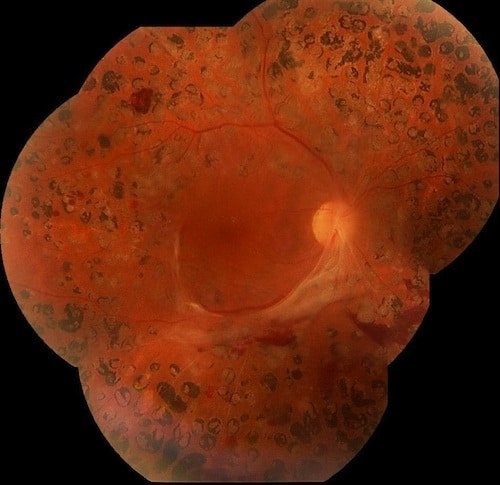

Retinopatía Diabética proliferativa con proliferación en meseta.

Aspecto del fondo de ojo luego de vitrectomia y endolaser.